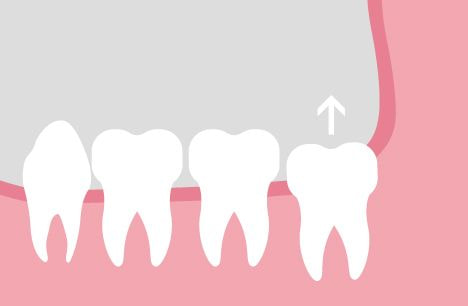

이런식으로 눕거나 매복하지 않고 바르게 난 사랑니는 통증도 거의 없고 염증이나 충치등 이상소견이 없으면 그대로 방치하기도 하는데